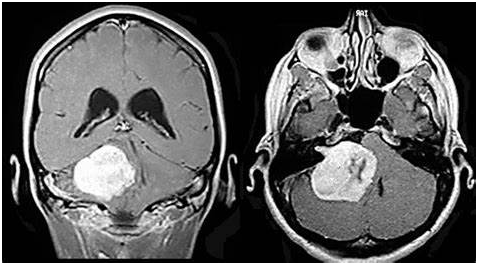

听神经瘤是一种颅内肿瘤,起源于八脑神经,称为前庭耳蜗神经,存在于内耳道或小脑桥角,位于后颅窝的颞骨岩部。它起源于由细胞构成的神经髓鞘。它从八脑神经的前庭部分开始。听神经瘤是根据大小来分类的。小肿瘤指的是小于1.5 cm的肿瘤。雪旺氏瘤属于1.5~2.5 cm的大小组。听神经瘤大于2.5 cm。

听神经瘤通常为小型脑瘤,生长缓慢,症状轻。如果手术切除的大小已经超过了其他的治疗方式带来的预后,病人应该选择这种治疗策略。治疗听神经瘤的效果也取决于医院现有的技术和外科医生的知识。在小型肿瘤中可以保留听力,手术后使用助听器可以支持听力,但切除肿瘤远比保留一侧耳朵的听力重要得多。